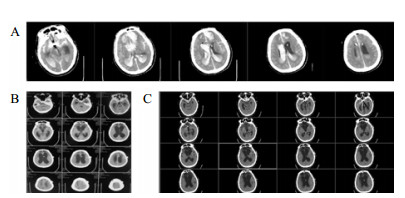

病例2,女,60岁,2017年10月以“动脉瘤夹闭和脑内血肿清除术后6个月,意识进行性下降2个月余“入院。入院时植物状态;查体:GCS 8分,双瞳孔3.0 mm,对光反应灵敏,双侧病理征阴性。右侧额颞部颅骨缺损大。入院头颅CT示脑室扩大。诊断为:右前交通动脉瘤术后、脑积水、头皮下积液、右额颅骨缺损、持续性植物状态(图 3)。

| 右侧额颞部颅骨缺损7 cm×9 cm,双侧脑室和三脑室扩大 图 3 2017年10月12日病例2的CT |

入院后于2017年10月30日行“颅骨修补+V-P分流术”。术后将分流管压力逐步调至0.5。患者术后意识无明显改善,复查CT示脑室仍显著扩大。观察2周后病情同前,遂将储液囊外接引流,每日引流量约200 mL,持续3 d,未见行为学及影像学明显变化。加大引流至每日300 mL,持续3 d后,患者自主睁眼增多;引流量增至每天400 mL左右,患者能呼唤下睁眼和视觉追踪。而停止脑脊液外引流后,患者则退步到引流前水平。决定通过按压储液囊促进脑脊液引流(按压600次/d),持续10 d后,睁眼时间延长但仍无意识。考虑到患者意识水平和引流量明显相关,增加按压储液囊频率至1 500次/d,患者又能呼唤睁眼,但CT未见脑室明显缩小。随后增加按压至2 000次/d时,偶尔能出现遵嘱活动,复查CT示脑室结构较前稍有缩小,但脑室仍显扩张。动态观察患者的行为学变化和反复CT随访,逐步升至4 000次/d,患者可表达简短言语,但脑室仍略扩大。随后每月按压次数递增1 000次直至6 000次,复查CT示脑室结构明显缩小(图 4A);患者意识显著改善,能简短正确对答。2018年6月病情稳定后,逐渐减少到3 000次/d, 并复查头颅CT(图 4B)。患者意识完全恢复,交流言语思路清晰,搀扶能行走。

| A:2018年3月27日头颅CT,此时6 000次/d,脑室系统明显缩小;B:2018年9月15日头颅CT,3 000次/d 图 4 病例2头颅CT |

病例3,患者男,76岁,因“突发头痛昏迷,动脉瘤栓塞脑室引流术后半年余,脑积水分流术后3个月”入院。入院体查:GCS 7分,植物状态,双巴氏征阳性。V-P分流调压阀压力为1.0,脑积水虽已行分流术,但脑室仍明显扩大。拟诊:左前交通动脉瘤栓塞术后,脑积水V-P分流术后,持续性植物状态。脑室压力低于外耳道连线5 cm, 持续外引流脑脊液100~200 mL/d,同时去枕卧位,腹带加压包扎,适当增加补液量和扩脑血管改善脑微循环,力求增加颅内压和脑顺应性。脑室压力逐渐上升,然后调压至0.5,期间多次复查未见脑室大小明显缩小;但患者出现对威胁有眨眼反应,偶尔能对视觉对象定位,转为微小意识状态。发病4年后,即80周岁时,因为肺部感染而再次入院,控制肺部感染期间,考虑脑室仍扩大状态,予按压分流阀600次/d,患者意识显著上升,能主动要求饮食并表达喜好,能和家属互动做简单游戏。随访头颅CT见脑室较前有所缩小(图 5C)。

| A:第一次入院CT(脑出血栓塞和脑室外引流后);B:常规治疗后脑室扩大仍明显;C:2018年7月5日随访 图 5 病例3 CT |

病例4,男,26岁,因“车祸致颅脑损伤昏迷6个月”而入我院。急诊行开颅血肿清除术后1个月因脑积水而行V-P分流术。入院体检:GCS 7分,植物状态,四肢肌张力高,双巴氏征阳性。入院诊断为:重型颅脑损伤术后,脑积水V-P分流术后,持续性植物状态(图 6A)。考虑V-P分流过度引流,将分流调压阀调至最高的2.5水平,骨窗压力和头颅CT没有明显改变。遂将分流管皮下缝扎完全阻断,骨窗压力逐渐升高,术后复查CT(图 6B), 同时患者意识水平改善至微小意识状态。因脑积水加重再行V-P分流术,并择期予右额颞颅骨修补重建,随访头颅CT见图 6C。随后患者恢复至GCS 15分。

| A:男,26岁,颅脑损伤术后6个月入院时头颅CT;B:2015年1月4日分流管缝扎后CT;C:2017年3月8日V-P分流和颅骨修补术后 图 6 病例4 CT |